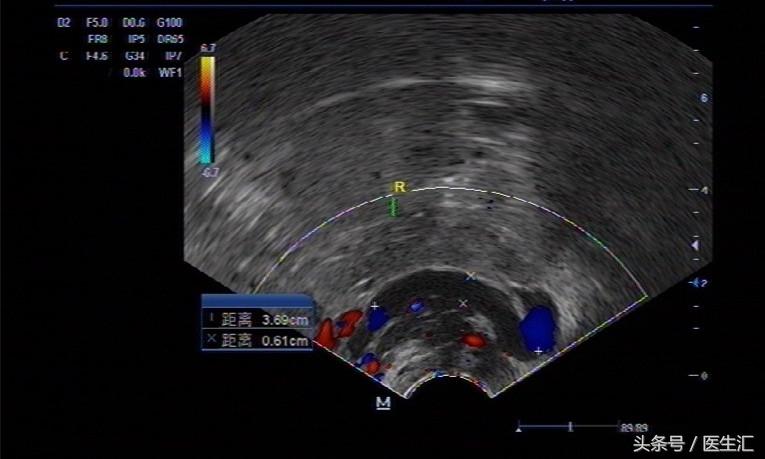

B超检查:子宫平位,大小约 77MM*50MM*37MM,实质回声稍匀均,内膜厚约 11MM,右附件区见一大小约49x42mm无回声区,边界清,左附件区见范围约53*27mm,杂乱回声区,内见一大小约11mm似孕囊回声区,子宫直肠窝处见深约11mm液性暗区,腹腔内可见液性暗区,肝肾隐窝较深约19mm,下腹腔较深约23mm。

1、左侧附件杂乱回声区,考虑宫外孕可能性大。

2、右侧附件区含液性包块

3、盆腹腔积液,后穹窿穿刺抽出血液 5ml。灯光下暗红色。

B超:子宫平位,大小约 77MM*50MM*37MM,实质回声稍匀均,内膜厚约 11MM,右附件区见一大小约49x42mm无回声区,边界清,左附件区见范围约53*27mm,杂乱回声区,内见一大小约11mm似孕囊回声区,子宫直肠窝处见深约11mm液性暗区,腹腔内可见液性暗区,肝肾隐窝较深约19mm,下腹腔较深约23mm。

提示 左附件杂乱回声包块内可见疑似孕囊回声。